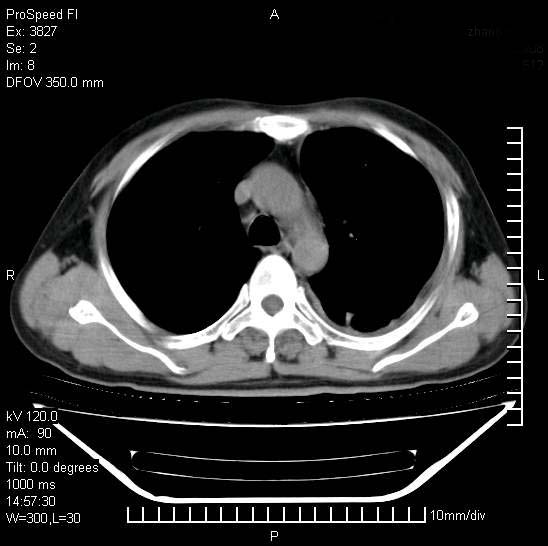

男性,一月前出现右侧肋区疼痛,较剧烈,干咳,无发热,自诉使用抗炎药后缓解,几天前又出现左侧剧烈疼痛,

发热,体温38。9,今天ct,考虑左侧包裹性脓胸,胸腔积液,右上中肺小斑片影,结核/炎症?胸水未见恶性细胞。

支持:脓胸!并双肺继发性肺结核!

左侧肺脓疡,化脓性胸膜炎(脓胸),不支持结核诊断,建议继续抗感染治疗